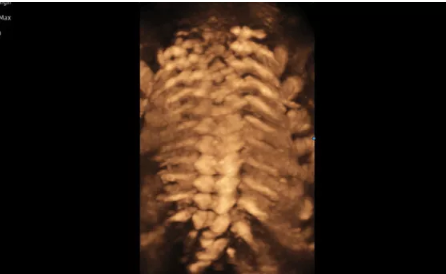

Hera i 10繼承并升級(jí)了全球首款5D超聲“三星麥迪遜WS80A”的“晶體結(jié)構(gòu)”成像理念,即將CrystalBeam?波束形成技術(shù)、CrystalLive?超聲成像引擎、S-Vue Transducer?視覺傳感器集于一身,提供更清晰的圖像。

3D/4D成像方面,Hera i 10通過結(jié)合先進(jìn)的圖像渲染技術(shù),著重加強(qiáng)了邊緣和小結(jié)構(gòu)的可視化能力。